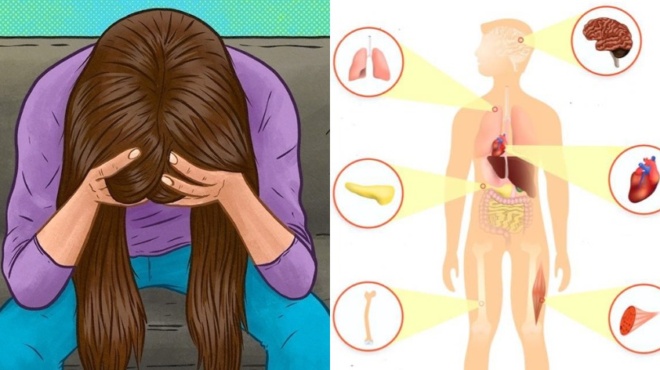

Βιταμίνη D: Η βιταμίνες ξέρουμε πως είναι πολύ σημαντικές για τον οργανισμό μας. Έχουμε όμως την πλήρη εικόνα για το τι κάνουν σε αυτόν;

Ποιο συγκεκριμένα θα μιλήσουμε για τις επιδράσεις που έχει η βιταμίνη D πάνω στον οργανισμό μας και τα οφέλη που προσφέρει.

Ποια είναι τα αίτια της ανεπάρκειας βιταμίνης D;

Τα προβλήματα στη μετατροπή της βιταμίνης D από τις τροφές ή την ηλιοφάνεια μπορεί να προκαλέσουν ανεπάρκεια. Παράγοντες που αυξάνουν τον κίνδυνο περιλαμβάνουν:

- Ηλικία 50 ετών και άνω

- Σκούρο δέρμα

- Ενα βορινό σπίτι

- Παραπανίσιο βάρος, παχυσαρκία, χειρουργική επέμβαση γαστρικής παράκαμψης

- Αλλεργία στο γάλα ή δυσανεξία στη λακτόζη

- Ηπατικές ή πεπτικές ασθένειες, όπως η νόσος του Crohn ή η κοιλιοκάκη

Βιταμίνη D: Συμπτώματα ανεπάρκειας

Οι περισσότεροι άνθρωποι με χαμηλά επίπεδα βιταμίνης D δεν παρατηρούν συμπτώματα. Μια σοβαρή ανεπάρκεια στους ενήλικες μπορεί να προκαλέσει μαλακά οστά, μια κατάσταση που ονομάζεται οστεομαλακία. Τα συμπτώματα περιλαμβάνουν πόνο των οστών και μυϊκή αδυναμία. Στα παιδιά, μια σοβαρή ανεπάρκεια μπορεί να οδηγήσει σε ραχίτιδα και συμπτώματα μαλακών οστών και σκελετικών προβλημάτων.

Καρδιακή νόσος

Τα χαμηλά επίπεδα βιταμίνης D έχουν συνδεθεί με μεγαλύτερο κίνδυνο καρδιακής προσβολής, εγκεφαλικού επεισοδίου και καρδιακής νόσου. Ωστόσο, δεν είναι σαφές εάν η αύξηση της βιταμίνης D θα μειώσει τους κινδύνους της καρδιάς.

Η σύνδεση της βιταμίνης D με την άνοια

Οι ηλικιωμένοι είναι πιο πιθανό να έχουν χαμηλά επίπεδα βιταμίνης D. Οι ερευνητές διαπίστωσαν ότι οι ηλικιωμένοι με ανεπάρκεια βιταμίνης απέτυχαν σε σημαντικό βαθμό σε τεστ μνήμης, προσοχής και συλλογιστικής, σε σύγκριση με τα άτομα που είχαν αρκετή βιταμίνη D στο αίμα τους. Ωστόσο, ακόμα απαιτούνται περισσότερες μελέτες για να μάθουμε εάν τα συμπληρώματα θα μπορούσαν να αποτρέψουν την άνοια ή να επιβραδύνουν την πνευματική κάμψη